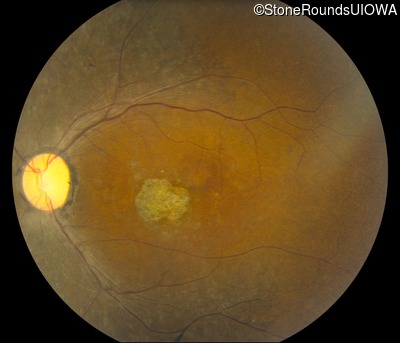

This 47 year old woman was born with a supernumerary digit on the ulnar side of both hands. As a young child, her best corrected visual acuity was completely normal. She had no difficulties with her vision until age 30 when her visual acuity could no longer be corrected to 20/20 and she began to notice some night blindness.

The clinical features supporting the diagnosis of Bardet Biedl syndrome in this patient include: bone-spicule-like pigmentation, narrowed arterioles and macular atrophy on ophthalmoscopy; photoreceptor loss on OCT; ulnar polydactyly, obesity, abnormal cognition, hypertension; and, normally sighted parents.